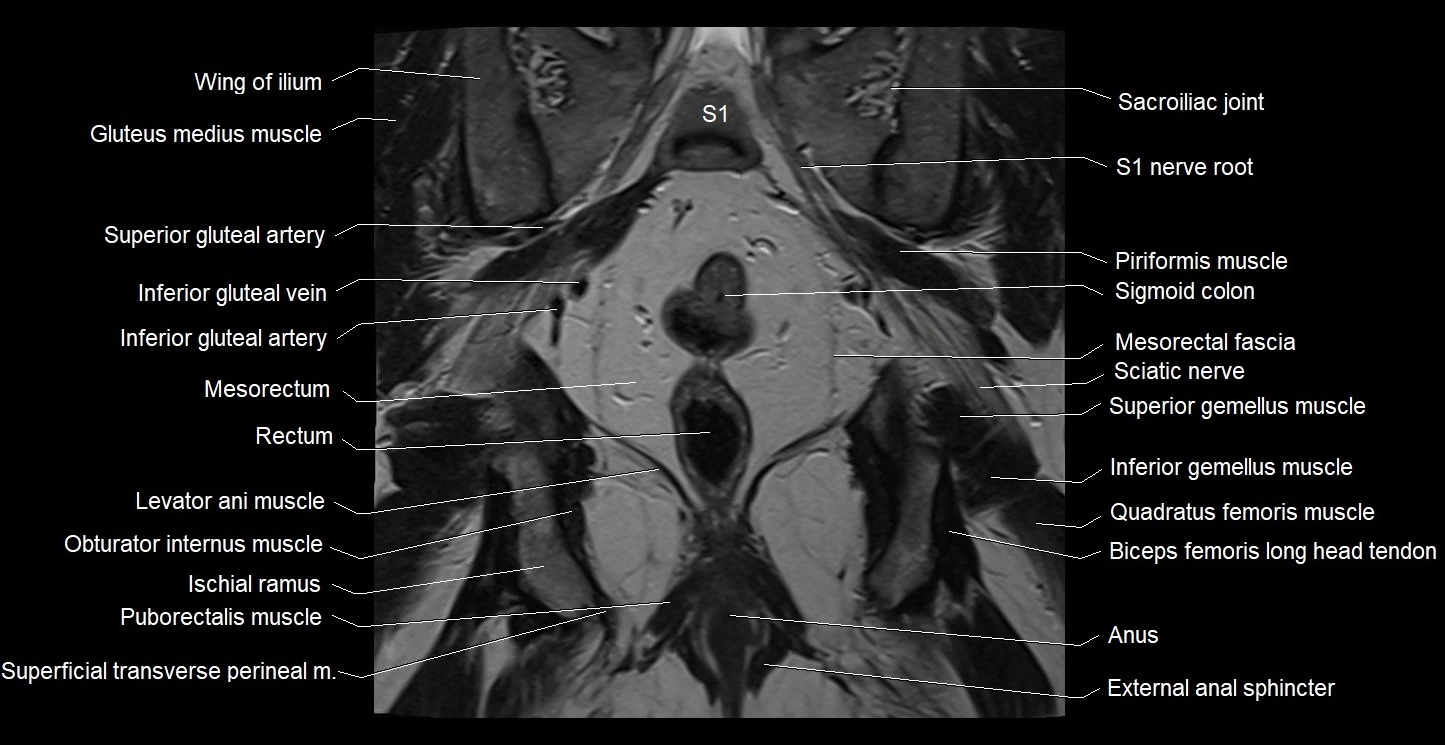

- External anal sphincter

- Inferior gemellus muscle

- Inferior gluteal artery

- Inferior gluteal nerve

- Inferior gluteal vein

- Levator ani muscle

- Median sacral crest

- Mesorectal fascia

- Mesorectum

- Obturator internus muscle

- Piriformis muscle

- Puborectalis muscle

- Quadratus femoris muscle

- Rectum

- Sacral plexus

- Sacroiliac joint

- Sciatic nerve

- Superficial transverse perineal muscle

- Superior gemellus muscle

- Superior gluteal artery